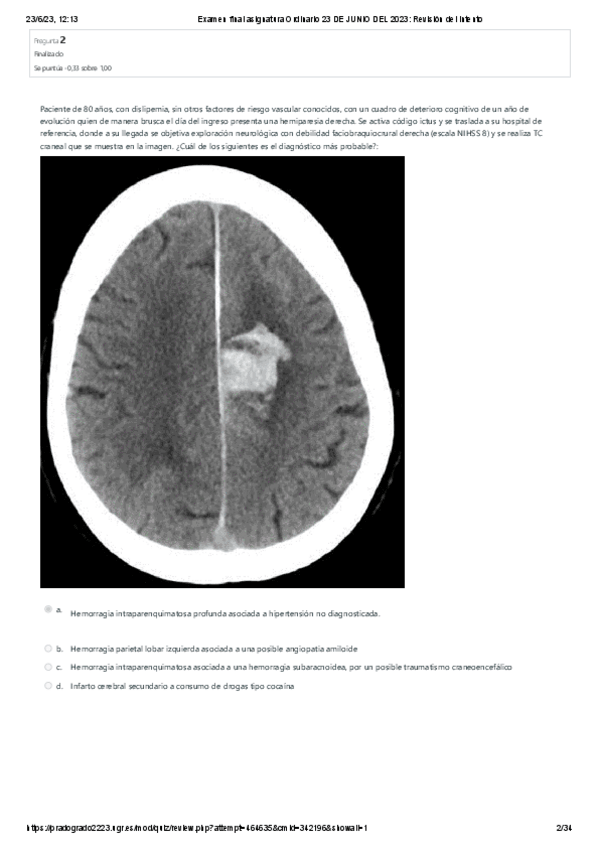

He publicado nuevos examenes de 4º Patología del Sistema Nervioso y Geriatría: EXAMEN-FINAL-NEURO-2023.pdf

34 páginas